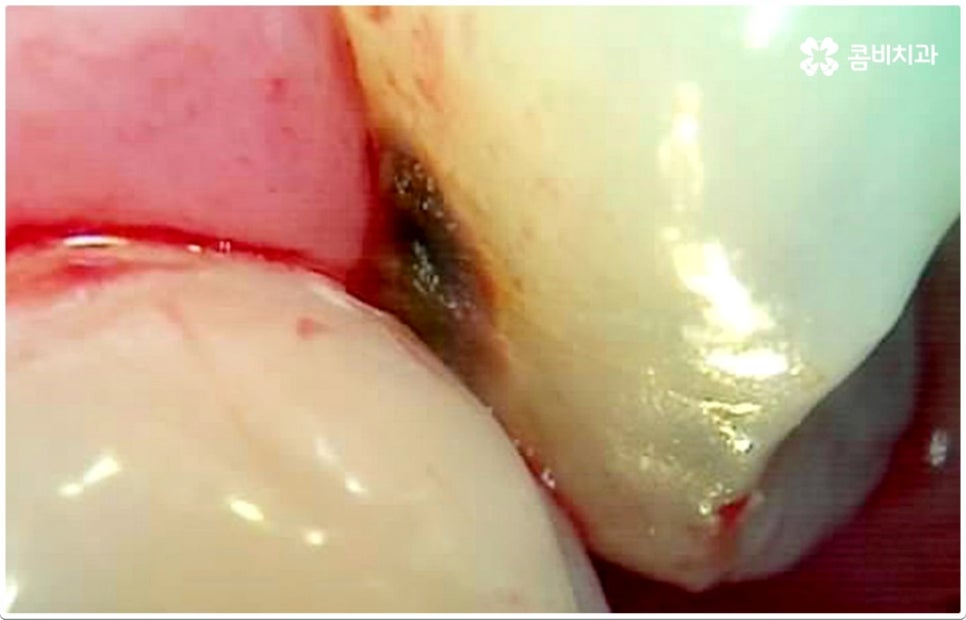

게다가 치아사이충치 는 두 치아의 인접면에 발생하여 한꺼번에 두 치아에 손상을 주기 때문에 보다 빠른 대처가 필요한데도 불구하고 말씀드린 것처럼 발견하기도 쉽지 않을 뿐더러 음식을 저작하는 치아의 교합면 (위아래 맞물리는 면) 에 생기는 충치가 아니기 때문에 수직으로 우식 부분까지 파고 내려가는 치과 충치 치료 기구들의 특성상 접근하기가 용이하지 않아 까다로운 진료에 속한다고 할 수 있어요. 특히 환자분들의 치아사이충치 발병 상황에 따라 치료 과정에서 부득이하게 삭제해야 하는 치아량이 생각보다 많아지는 케이스가 있을 수 있으므로 이에 대해 잘 알아두실 필요가 있습니다.

즉 환자분들이 느끼시기에는 육안으로 확인되는 우식 부위가 작은 것 같아도 안쪽으로 깊이 손상이 진행된 치아사이충치 케이스가 있을 수 있는데요. 이 때 맞닿은 치아 옆 면이 완전히 무너질 정도로 손상되었다면 이를 자연스럽게 복원하기 위해서는 레진으로 직접 때워주는 초기 충치 치료 방식을 사용하는 것은 적합하지 않고 인레이 치료를 통해 수복하는 방식이 필요하며, 레진 치료가 대부분 하루 만에 끝나는 비교적 간단한 것이라면 인레이 치료는 삭제한 부위에 딱 맞는 보철물을 만들어야 하기 때문에 시간도 더 오래 걸리고 비용도 커질 수 있으므로 환자분들께서 의료진과의 충분한 상담을 통해 자신의 상황이나 일련의 치아사이충치 치료 과정에 대해 그 필요성을 먼저 정확하게 이해한 후 치료를 받으시길 권유드리고 있어요. 만약 자체 기공소를 갖추고 있는 치과라면 환자분들에게 딱 맞는 보다 섬세하고 정교한 보철물 제작이 훨씬 빠르게 이뤄질 수 있다는 점에서 시간적인 부담을 줄여드릴 수 있으니 이 부분을 체크해 보시는 것도 좋을 거예요.